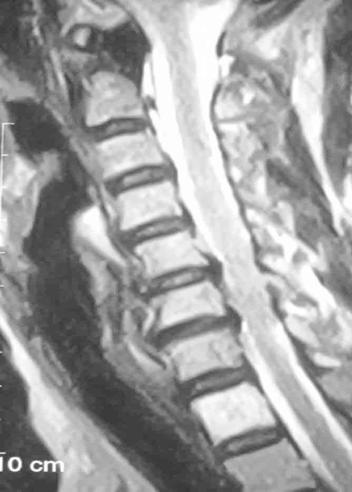

何女士术前核磁检查显示:多节段颈椎间盘退变导致神经根炎症产生